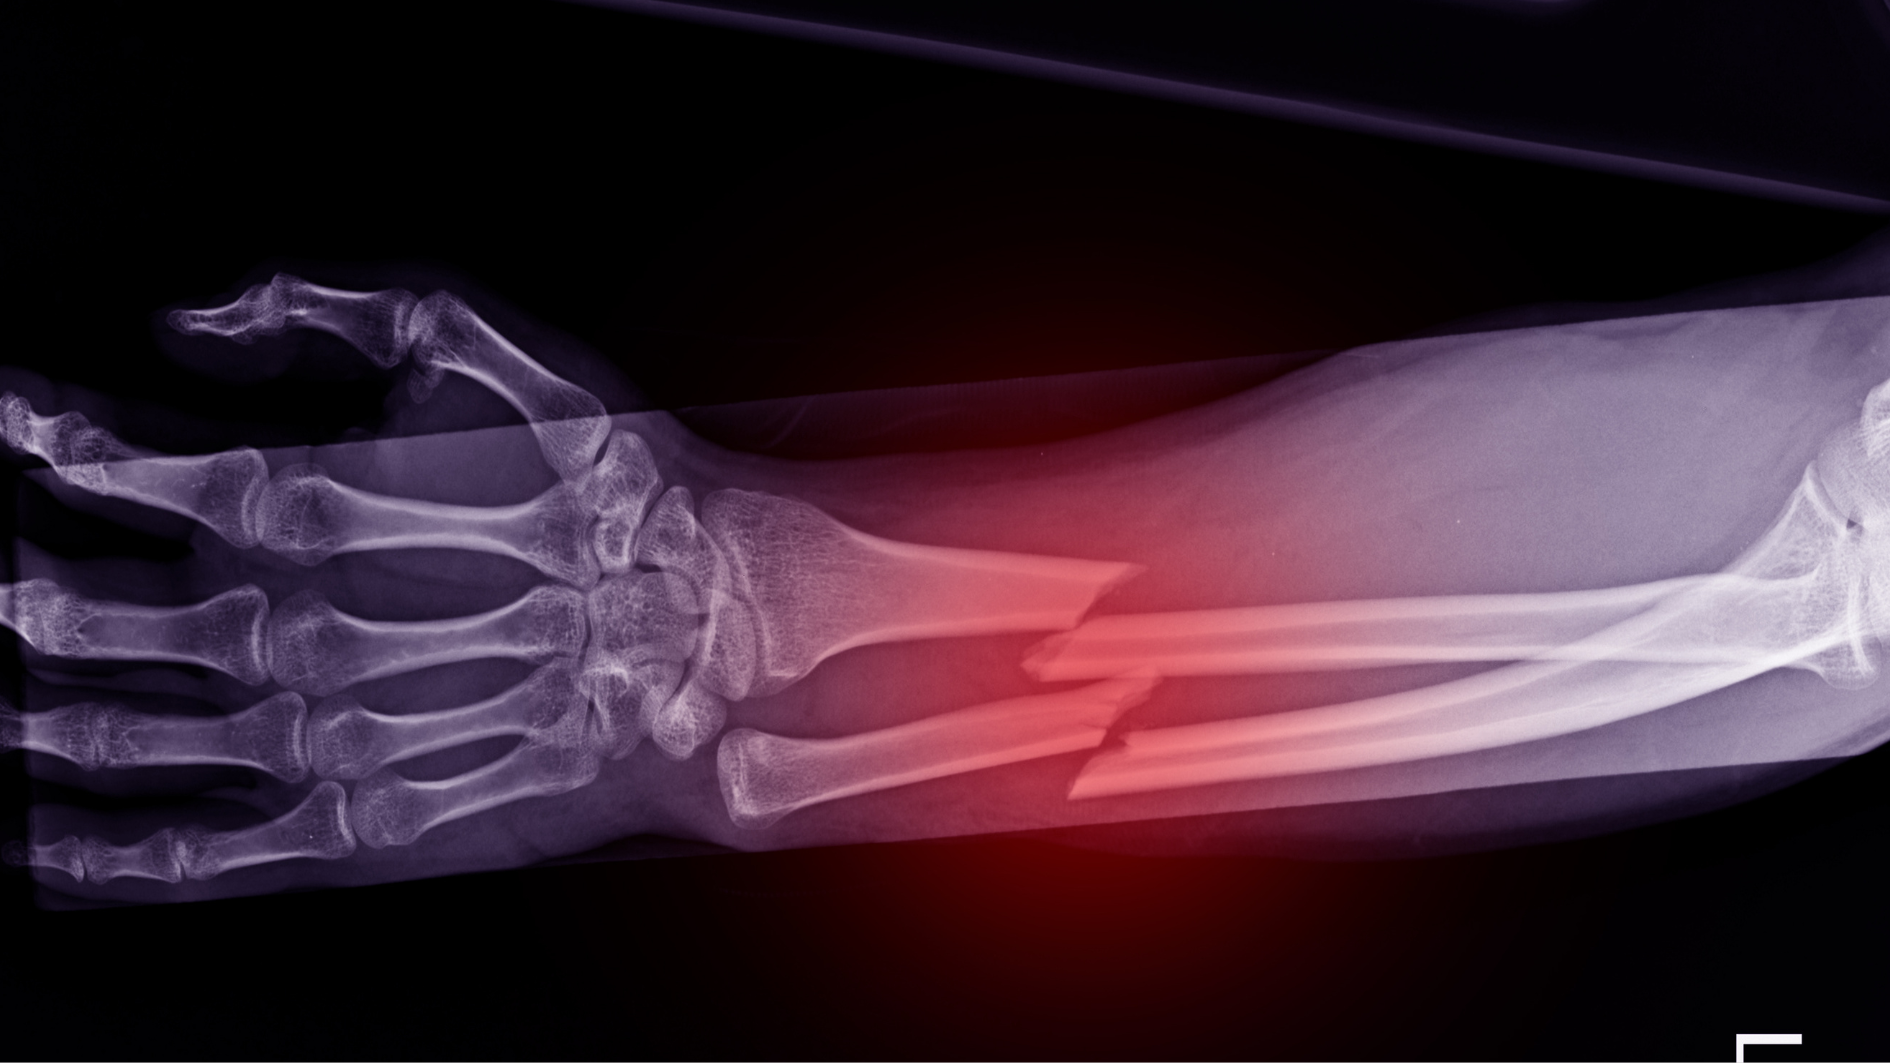

Nếu nứt xương nghiêm trọng hoặc không ổn định, bác sĩ có thể chỉ định can thiệp phẫu thuật. Phương pháp này thường sử dụng kim, vít, hoặc nẹp để cố định vết nứt, đảm bảo xương được liền lại đúng vị trí và tránh biến dạng. Phẫu thuật thường được áp dụng cho các trường hợp nứt xương ở vị trí chịu lực lớn hoặc nứt xương phức tạp, khó lành tự nhiên.